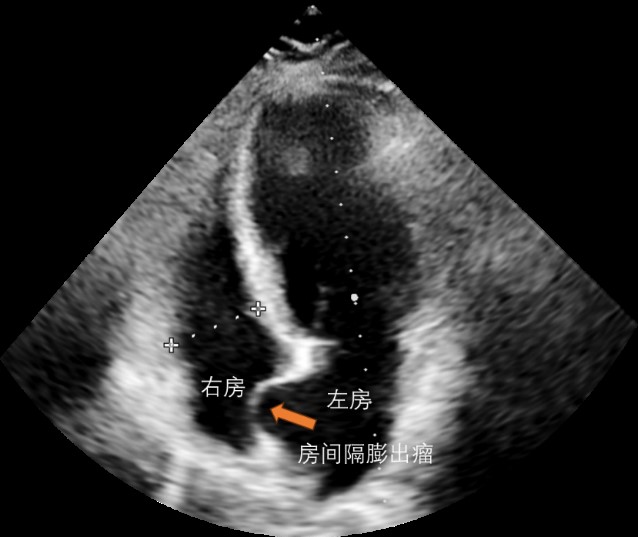

经胸超声心动图下的房间隔膨出瘤

房间隔膨出瘤是如何发现的?超声心动图是诊断房间隔膨出瘤最简便可靠的方法,能显示瘤体的位置、大小情况,经食管超声心动图是检查是否合并卵圆孔未闭的金标准。此外,计算机断层扫描、心脏磁共振以及心腔内超声、心脏血管造影也可诊断出该疾病。

经食道超声心动图下的房间隔膨出瘤及卵圆孔未闭